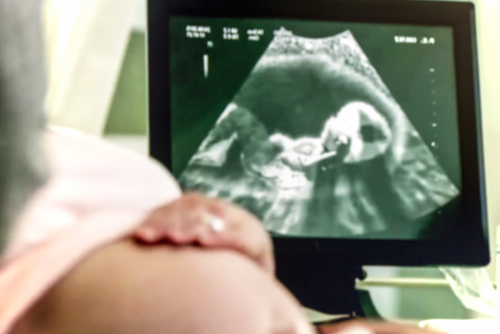

前置胎盤・低置胎盤は経腟超音波(エコー)検査で胎盤の位置を確認して診断します。妊娠中期に前置胎盤・低置胎盤が疑われても、妊娠の経過とともに、子宮が大きくなって胎盤の位置が上方にずれ、子宮口から離れていくことがあります。妊娠週数により前置胎盤・低置胎盤の治る確率は変わるため、経腟エコーによる確定診断は妊娠24週以降が望ましく、31週末までに行います。

前置胎盤の妊婦さんのうち、帝王切開を経験したことがある方は、癒着胎盤を合併する確率が高いことから、MRI検査をして癒着の有無を調べることもあります。ただし、癒着胎盤を分娩前に確定診断することは難しく、前置胎盤では癒着胎盤の合併を常に考慮に入れる必要があります。

なお、前置胎盤の可能性がある場合、内診による診断は禁忌となっています。 指で胎盤の裏側をこすることで、大出血のリスクがあるためです。